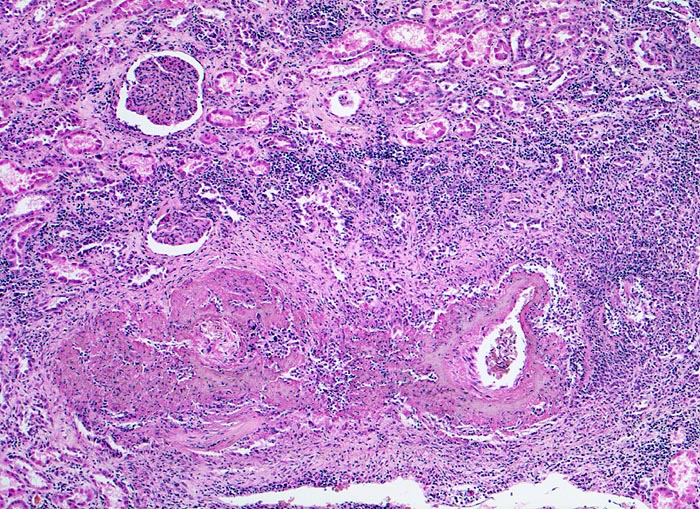

Polyarteritis nodosa Makroform

Unten im Bild eine grössere Arterie mit einer praktisch die ganze Zirkumferenz erfassenden Gefässwandnekrose. Kappenartig der Nekrose aufsitzende Entzündungsinfiltrate. Im tubulo-interstitiellen Raum sind fokale lymphohistio-plasmozytäre Infiltrate vorhanden. Geringe interstitielle Fibrose.

Makroskopischer Befund der Nieren: Vergrösserte Nieren mit Petechien und mehreren frischen, teils hämorrhagischen Infarkten.

Seit einigen Wochen Fieber unklarer Ätiologie, Gewichtsverlust und Anämie. Im Rahmen der Abklärungen erstmals festgestellte arterielle Hypertonie. Der Patient verstirbt an einem Myokardinfarkt.